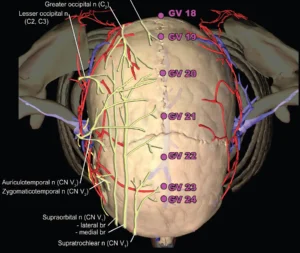

Meridian Zarządzający DU20 "Baihui"

- Rzut oka na lokalizację anatomiczną GV20 i kilku pozostałych punktów wzdłuż meridianu GV (kolorowe ryc. człowiek, MRI proj.strzałkowa: pies)

Nanda G. Robinson " Interactive Medical Acupuncture Anatomy" Tenton Newmedia 2016

- Okolica GV20 jest unerwiana przez nerw czaszkowy V (nerw trójdzielny oraz nerwy z odcinka szyjnego C2 i C3 (m. in. nerw potyliczny mniejszy i większy)

- Podrażnienie nerwu trójdzielnego jest jednym z głównych powodów bólu w obrębie głowy i twarzy.

- Tłumaczy to zastosowanie punktu DU 20 w neuralgii n. trójdzielnego oraz bólach głowy oraz innych zaburzeniach kompleksu trójdzielno-szyjnego (trigeminocervical complex), które spowodowane są często przez problemy stawu skroniowo-żuchwowego, przewodu słuchowego zewnętrznego lub zwyrodnienia odcinka szyjnego